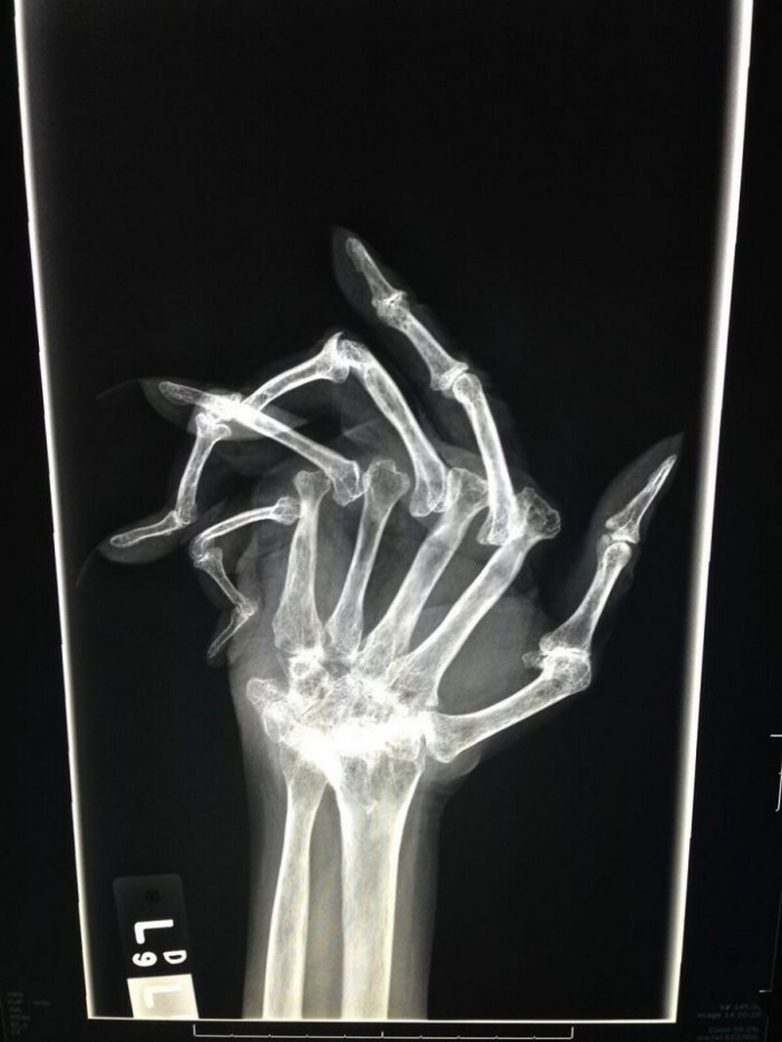

Тяжелый случай ревматоидного артрита на рентгене